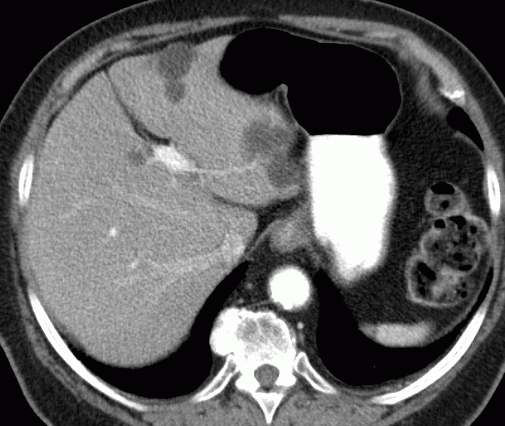

| Lebermetastasen | Lebermetastasen bei Plattenepithelkarzinom des linken Lungenunterlappens.![]() |